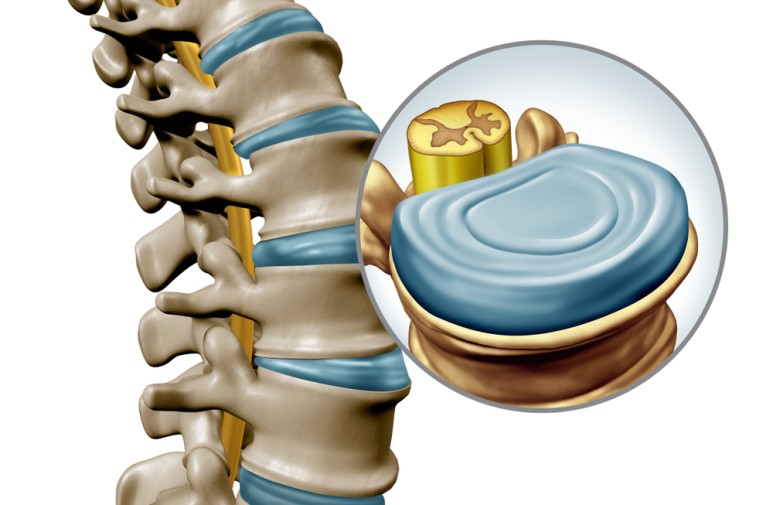

1. 척추의 모습

진료실 책상 위에 디스크 모형이 있지만, 미리 알고 있으면 좋겠죠.

1) 26개의 뼈로 구성

목뼈인 경추 7개, 등뼈인 흉추는 12개, 허리뼈인 요추는 5개,

엉치뼈인 천추는 5개, 꼬리뼈인 미추는 4개로 이루어져 있습니다.

하지만 성인이 되면 5개의 천추가 하나로 합쳐지고,

4개의 미추가 하나로 합쳐지게 됩니다.

하나로 합쳐진 천추와 미추는 각각 천골, 미골이라고 불리며

이로 인해 성인의 척추뼈개수는 총 26개로 구성되어 있습니다.

2) 척추는 S자 모형의 곡선 이루고 있습니다.

2. 디스크에 대해 이해하기

1) 디스크는 척추 뼈와 뼈사이에 있는 물렁한 치즈같은 것이에요.

2) 얇은 막이 여러겹 둘러 쌓인 형태이고 이걸 섬유륜이라 불러요.

3) 디스크는 찢어지면서 염증을 발생시켜요.

4) 찢어졌다고 다 통증이 있는건 아니고 통증의 정도가 사람마다 다를 수 있어요.